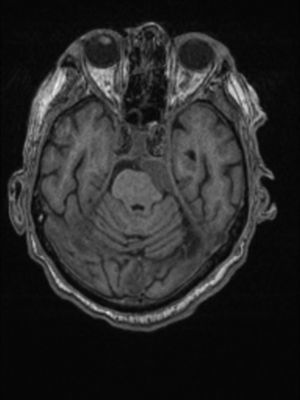

Paciente de 73 años con adenocarcinoma de próstata estadio iv, desde hace diecinueve meses, por afectación ósea múltiple y hepática única, tratado con radioterapia pélvica, hormonoterapia, y dos líneas de quimioterapia. Como antecedentes de interés destacan enfermedad de Parkinson, diabetes mellitus tipo 2, hipertensión arterial y hábito tabáquico. Presenta, desde hace doce meses, disfunción del nervio hipogloso mayor izquierdo que se puso en relación con una lesión ósea en la base del cráneo por la que recibió radioterapia paliativa. Hace siete meses comenzó con diplopia por parálisis del músculo recto lateral del ojo izquierdo atribuida a neurotoxicidad por los tratamientos recibidos. Meses después presentó también paresia del músculo recto lateral del ojo contralateral. Acude a revisión por deterioro general. En la consulta se aprecia discreta desviación de la comisura bucal izquierda. Una exploración más detallada permite detectar hipoacusia ipsilateral, disfagia y desviación lateral de la cabeza hacia la izquierda, de nueva aparición. Se desestima la realización de una punción lumbar diagnóstica por deseo del paciente de limitar la realización de maniobras invasivas. Se realiza una RM cerebral de la que se obtienen las imágenes que se presentan (figs. 1 y 2).

En la RM cerebral se objetivó una masa dural que ocupaba el ángulo pontocerebeloso izquierdo, extendiéndose cranealmente por la vertiente izquierda de la cisterna prepontina hasta el seno cavernoso de ese lado, con dudosa infiltración del tronco encefálico. Se descartaron lesiones isquémicas de evolución aguda y/o signos de carcinomatosis leptomeníngea. Ocupación mastoidea izquierda ya conocida sin cambios respecto a exploraciones previas.